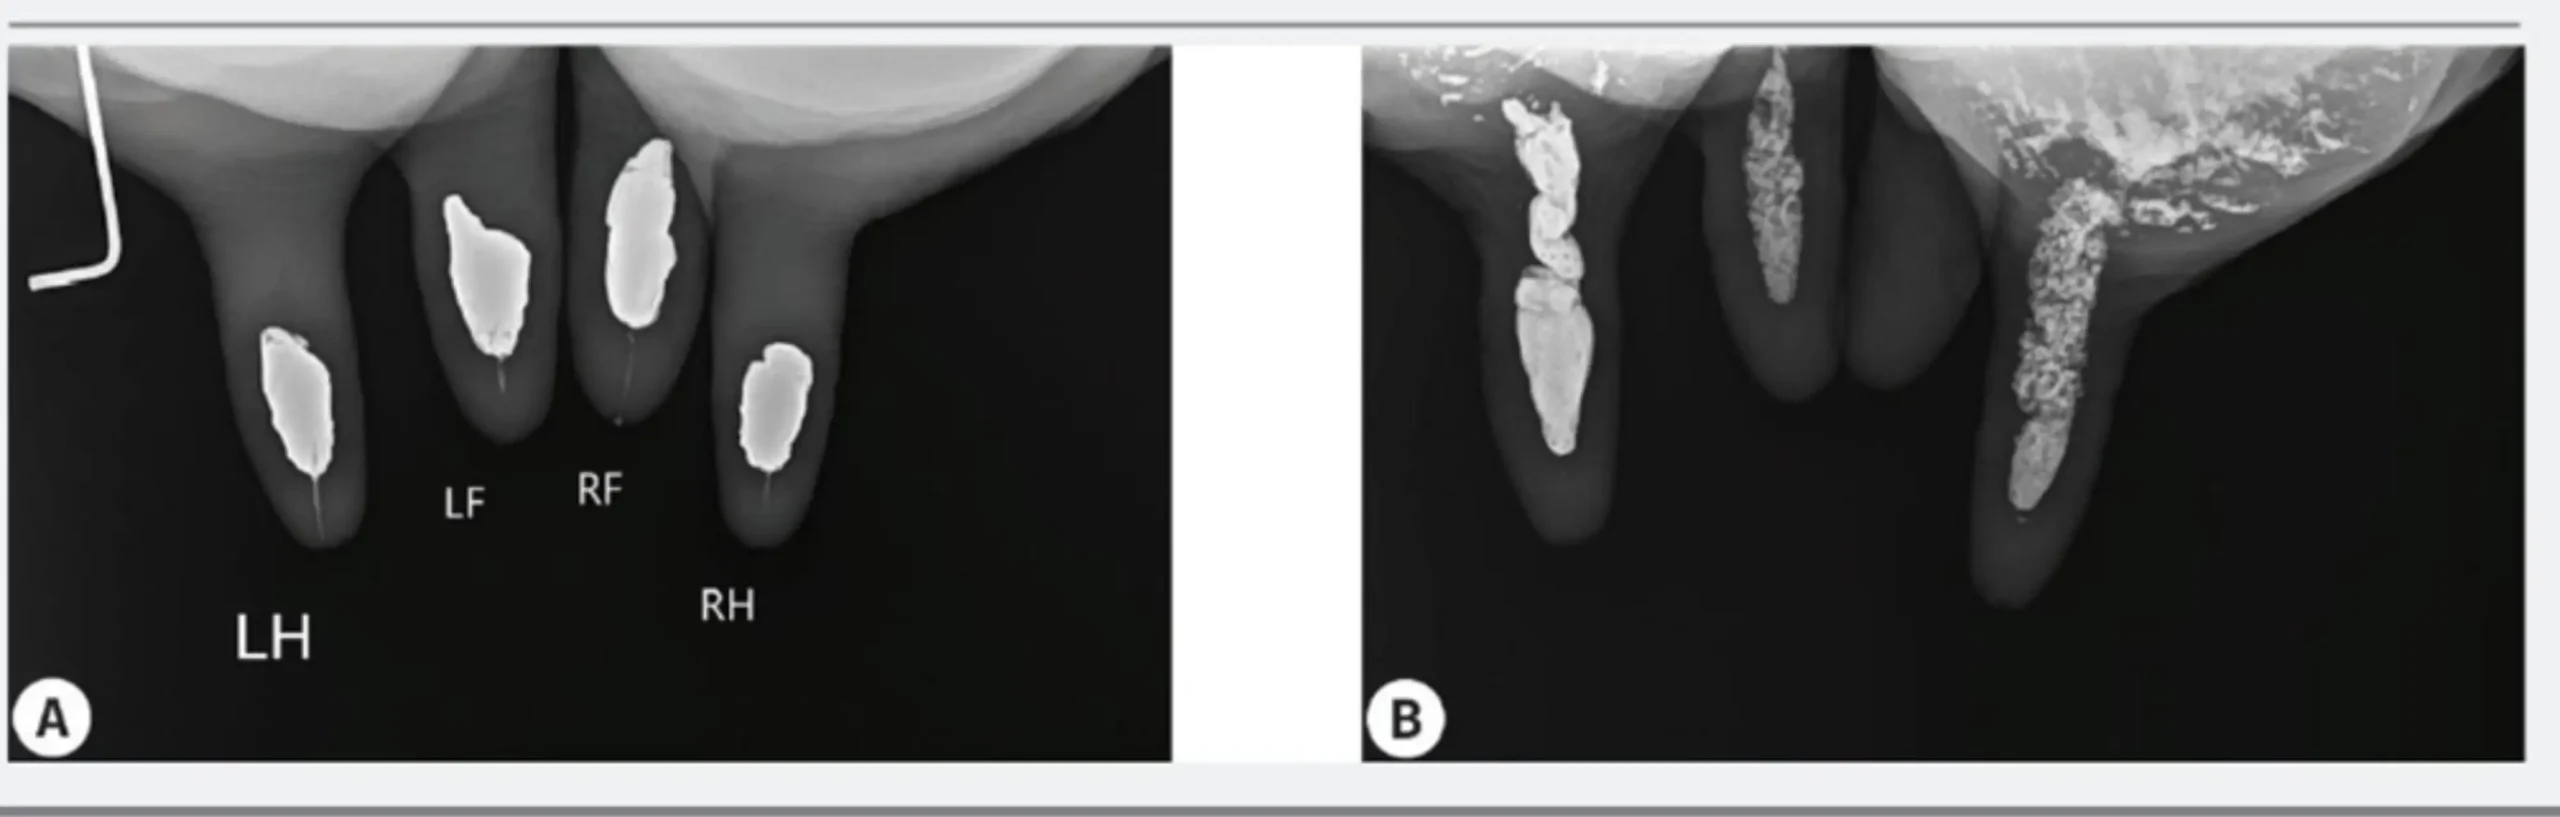

I sigillanti a base di bismuto disponibili in commercio, in preparati da 4 e 6 grammi, vengono inseriti all’interno del capezzolo, talvolta in combinazione con antibiotici chemio-attivi. Essi mantengono la loro posizione iniziale per un periodo medio di 3-4 settimane, dopodiché migrano nella cisterna e nella ghiandola mammaria in percentuali variabili (vedi foto).

La migrazione, che avviene durante il periodo di asciutta (figura-3, confronto della posizione del sigillante durante l’asciugatura (DO) e nell’imaging pre-fresco (PF) per le diverse aree: canale di striature, cisterna per capezzoli e ghiandola), influenza la rilevazione del materiale al momento del parto e nel periodo successivo. Infatti, alla prima mungitura dopo il parto, solo l’83% degli animali trattati presenta il tappo sigillante in modo evidente. Il restante 17% mostra l’assenza totale del materiale nel canale striato del capezzolo, anche se esso è distribuito nel sistema alveolare nel 56% dei casi (Buckley (2022): studio sull’efficacia dei sigillanti endomammari a base di bismuto).

Durante la prima mungitura, le bovine con una bassa conta delle cellule somatiche trattenevano il 45% del materiale inoculato, mentre quelle con una conta elevata ne trattenevano solo il 23% (vedi figura in basso). Questo potrebbe essere dovuto al volume totale inoculato (sigillante più antibiotico), che causa un diverso posizionamento e riempimento del canale striato.